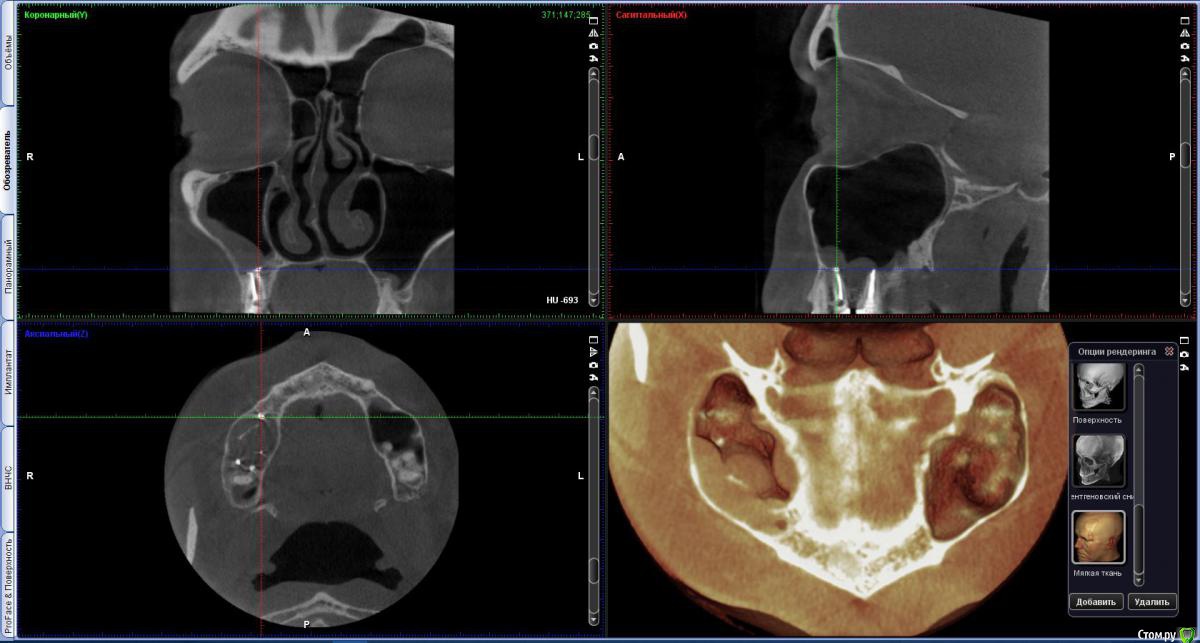

vicTORYa Опубликовано 6 октября, 2016 Автор Поделиться Опубликовано 6 октября, 2016 (изменено) Здравствуйте. Сделала КТ зубное, на 5 нижем правом зубе показалось что есть пятно странное. Подскажите не киста ли это? http://s016.radikal.ru/i337/1610/c3/a4db31326fc5.jpg Изменено 6 октября, 2016 пользователем vicTORYa Ссылка на комментарий

vicTORYa Опубликовано 23 октября, 2016 Автор Поделиться Опубликовано 23 октября, 2016 Скажите пожалуйста понятно ли что-то на этом КТ?С момента их лечения прошло чуть больше года, ждала не ставила коронки посмотреть не дадут ли проблемы зубы, в которых выведен материал, можно ли на данный момент сделать какие-то выводы? 6 и 7 не беспокоят, а вот 5 немного побаливает иногда. Просто иду на следующей неделе ставить коронки, всё ли в порядке с зубами, можно ли ставить коронки? Перелечивать так на всякий случаи не хочется, а только если там возникнет проблема. У мужа тоже есть один зуб с выведенным материалом и ему уже больше 10 лет и нет с ним проблем. Вот и думаю перелечивать только в случае необходимости.Сделать новый ренген не могу очень много уже сделал ренгенов за этот год. Ссылка на комментарий